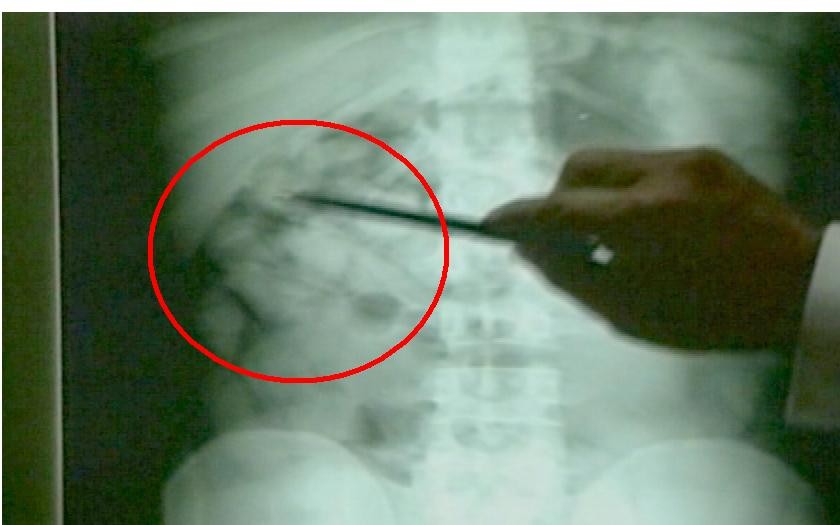

Colníci tušili, že Ladislav ukrýva aj niečo viac, preto ho eskortovali na bratislavské Kramáre. Tu sa mladík priznal, že v tele pašuje 15 kapsúl kokaínu. Následne vykonali u dvoch mladíkov domovú prehliadku, vďaka ktorej zaistili 100 gramov marihuany a 5 gramov bielej látky. V jednom byte našli takmer 6 tisíc €. Všetkým mladíkom, ktorí sú obvinení z drogovej trestnej činnosti, hrozí až 20-ročný pobyt za mrežami.